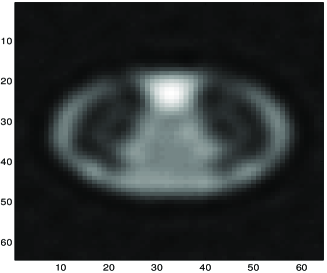

Fig. 8 shows results obtained in X-ray tomography image reconstruction. In this figure a) shows the original image, b) shows the projections (data), c) shows the backprojection reconstruction, d) shows a reconstruction using a Gaussian prior, e) shows a reconstruction using a Gamma prior, and f) shows a reconstruction using GNC with truncated quadratic regularization.

|

|

|

| a | c | e |

|

|

|

| b | d | f |

a) original, b) projections (data), c) Backprojection, d) Gaussian reconstruction, d) Gamma prior reconstruction, and e) GNC reconstruction